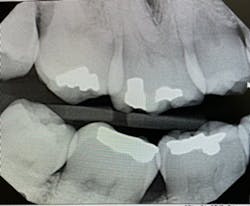

Figure 1 indicates that the PID is not parallel to the interproximal surfaces, causing severe horizontal overlap in both the maxilla and mandible. The radiographic image would be considered undiagnostic. The ideal method used for an excellent bitewing is to have the central beam parallel to proximal surfaces.

Literature suggests using the “open-door method” when contacts need to be clear and diagnostic.5 This method is achieved by moving the sensor distomesially by 15 degrees to ensure the canine is visible. This will keep the interproximal spaces open in the premolar bitewing. To avoid horizontal overlap, the central ray should be perpendicular to the arch of the teeth and directly through the interproximal spaces. With proper training and education on the concepts to mitigate overlapping, we can avoid exposing our patients to unnecessary radiation. Unfortunately, because the angle of the PID is off in Figure 1, the patient will need to be exposed to another radiograph. Proper angulation is shown in Figure 2, and proper positioning of the open-door method is shown in Figure 3.